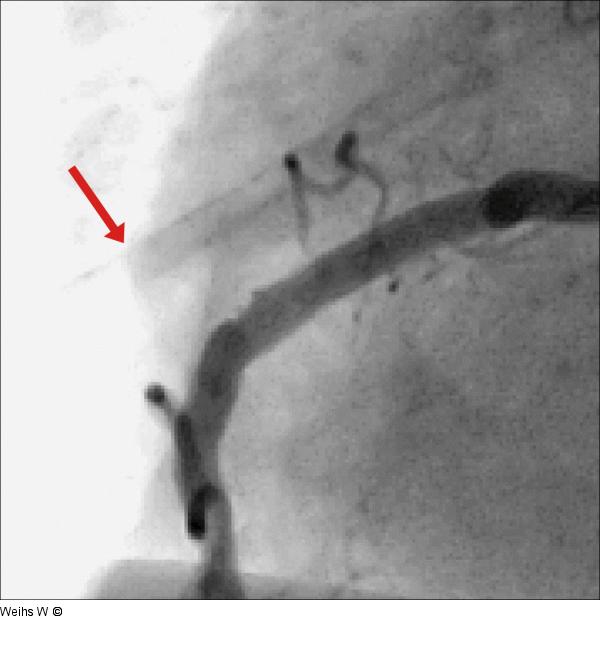

Abbildung 4: RCA

Vergrößerter Detailausschnitt von Abbildung 3